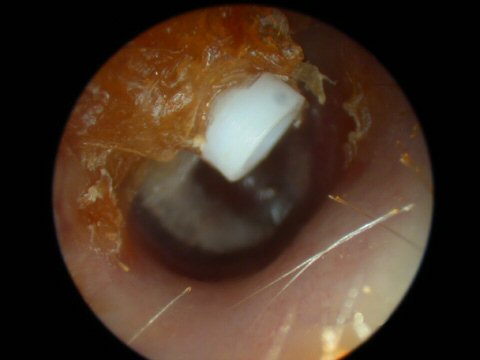

Ear tubes - The first picture shows an ear tube that has fallen out but is stuck to ear canal by ear wax. The last picture shows a T-tube, these stay in place much longer but run the risk of leaving a permanent perforation when finally removed.